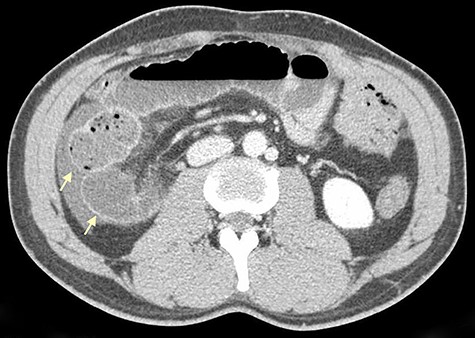

On physical examination, he was eupneic, hemodynamically stable and apyretic. His abdomen was soft, not distended, painless, with normal bowel sounds. Rectal examination showed an empty ampulla. Blood analysis revealed mild leukocytosis and little increase in C-reactive protein. Plain radiograph of the abdomen revealed dilated small bowel loops with air/fluid levels. Abdominal ultrasound revealed swollen intestinal loops on the right flank and interloop fluid. For further clarification, abdominal and pelvic computed tomography (CT) scan showed small bowel distension, air/fluid levels and free fluid (Fig. 1); signs of intestinal malrotation, with alteration of the normal topography of the duodenal arch (Fig. 2) and retrocecal position of terminal ileum (Fig. 3).

Coronal CT scan shows signs of intestinal malrotation, with alteration of the normal topography of the duodenal arch (arrow).